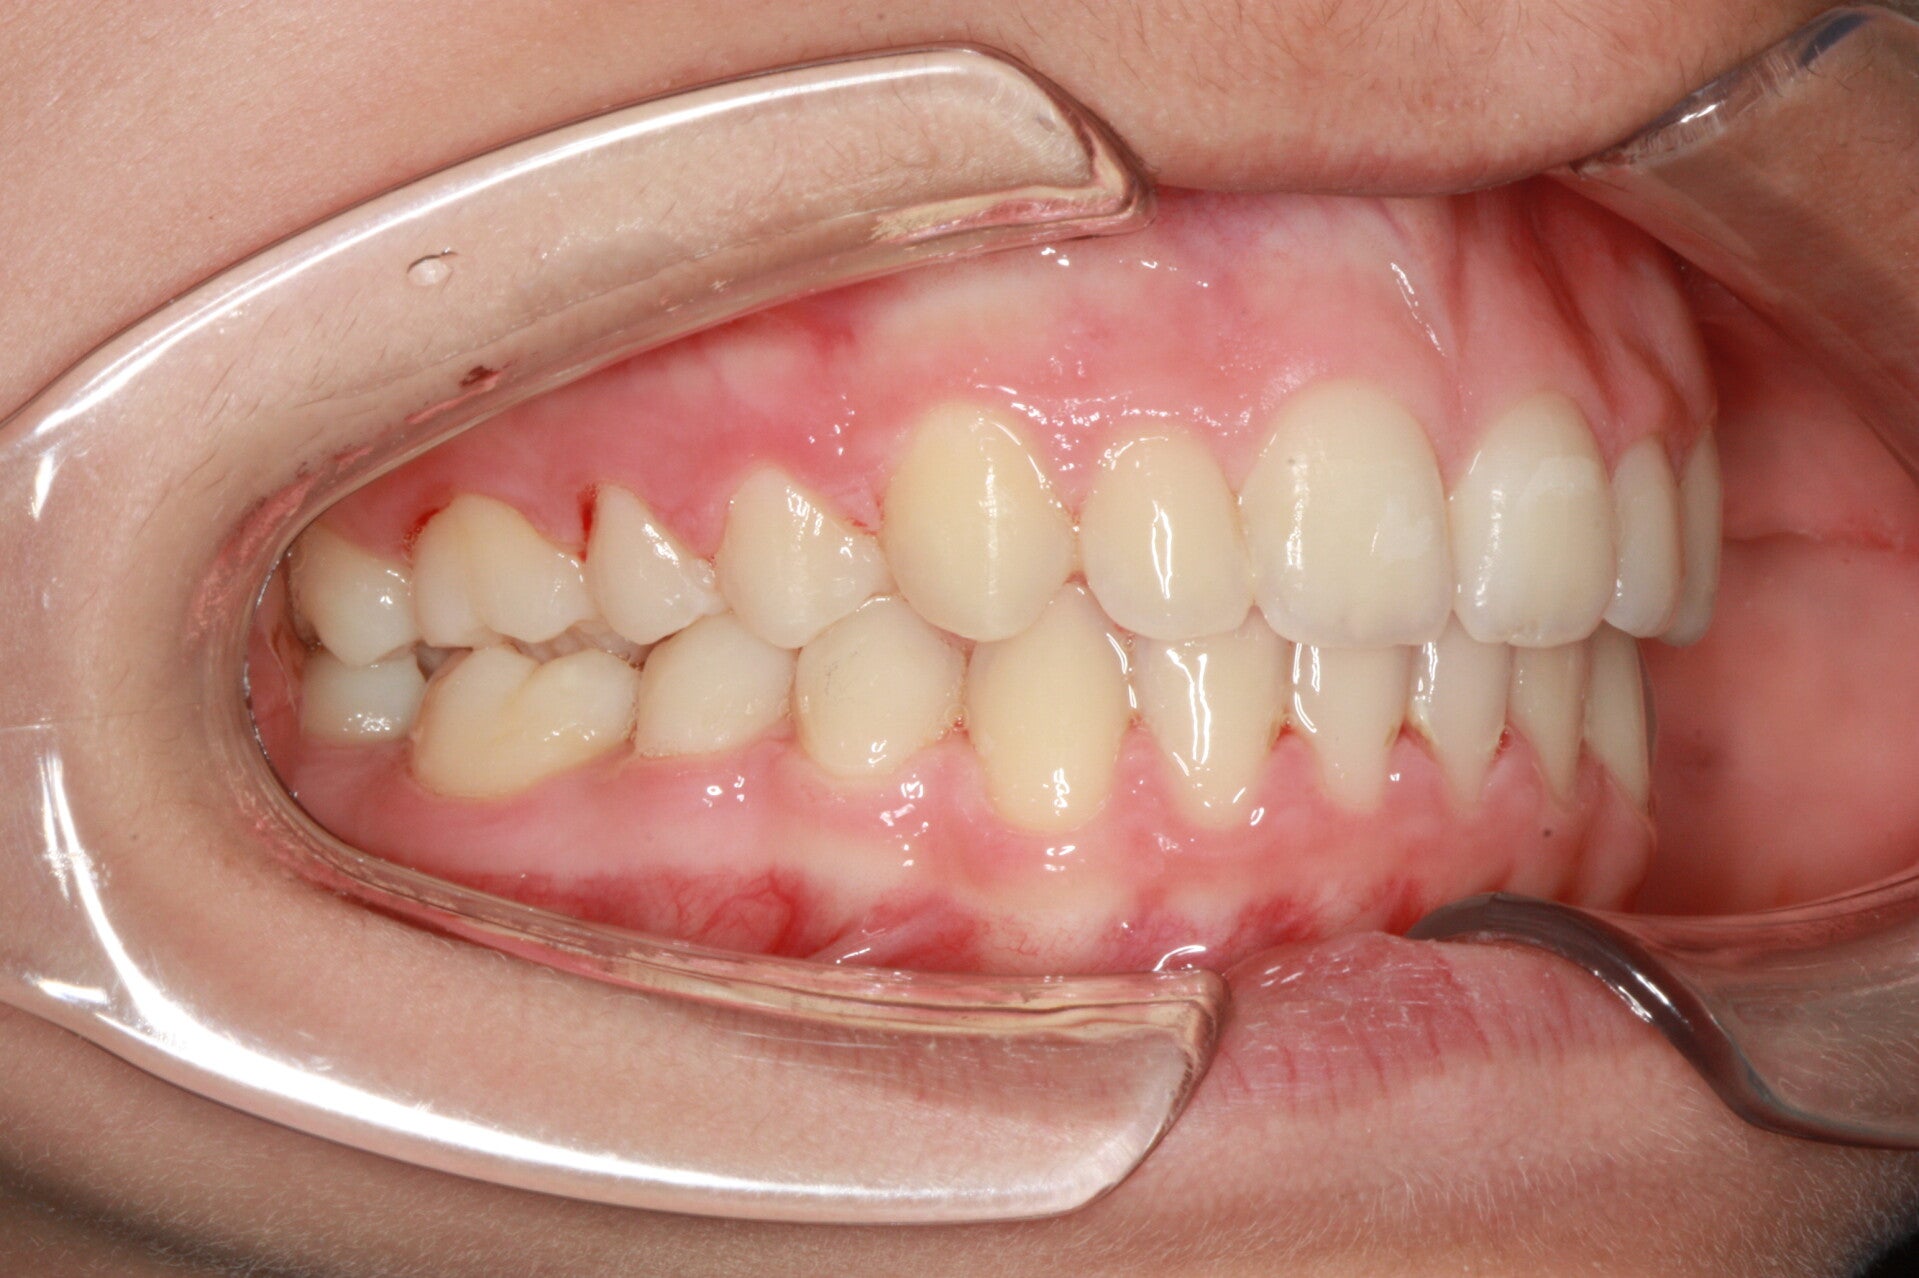

Questo mese vi presentiamo G.G. f. di15aa. Ha una seconda classe suddivisione destra molare e canina. richiesta Allineamento.

FOTO INIZIALI PRE TRATTAMENTO ORTODONTICO

FOTO FINALI DOPO 24 MESI CIRCA DI TERAPA ORTODONTICA FISSA